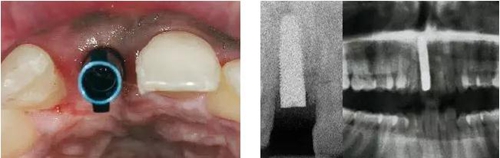

圖1、該病例顯示了厚齦生物型和中弧線形齦乳頭形態(tài)。右上中切牙由于牙根縱裂而需要拔除。由于該患牙伸長(zhǎng),使得軟組織量垂直向增加。牙齦色素沉著是個(gè)美學(xué)挑戰(zhàn)。

圖4、植入的種植體,初始穩(wěn)定性很好,由于骨缺損范圍大,選擇潛入式愈合。

圖5、種植體完全位于拔牙窩骨壁包圍的范圍內(nèi),距離唇側(cè)骨板至少2mm。

圖9、種植體植入5個(gè)月:種植體到唇側(cè)骨板的距離仍然大于2mm,這對(duì)于形成長(zhǎng)期穩(wěn)的美學(xué)效果有很重要的作用。

圖10、剛植入種植體當(dāng)天的情況(左)和植入種植體1年時(shí)的情況(右)。